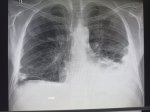

Здравствуй двачик, сегодня мы с вами опять будем играть в рентгенолога, я вам буду постировать фоточ

Здравствуй двачик, сегодня мы с вами опять будем играть в рентгенолога, я вам буду постировать фоточки, а вы узнавать пиздецомы на них.

А пока мы обсуждаем этот сложный вопрос я вам фоочки буду показывать! Штош погнали!

Гидроторакс с линией демуазо?

Ну чот, а метастазы чому игноришь?

Хм, так понимаю увеличены сердце и магистральные сосуды, которые дают такую мощную тень?

Гидрач слева и множественные очаги

На пикрилле я так пологаю тяжело заболевание имя ему что то между хранический пиздец и рак 40 стадии, в любом случае пациенту я конечно не врач, но учитывая область поражения, не жить

image